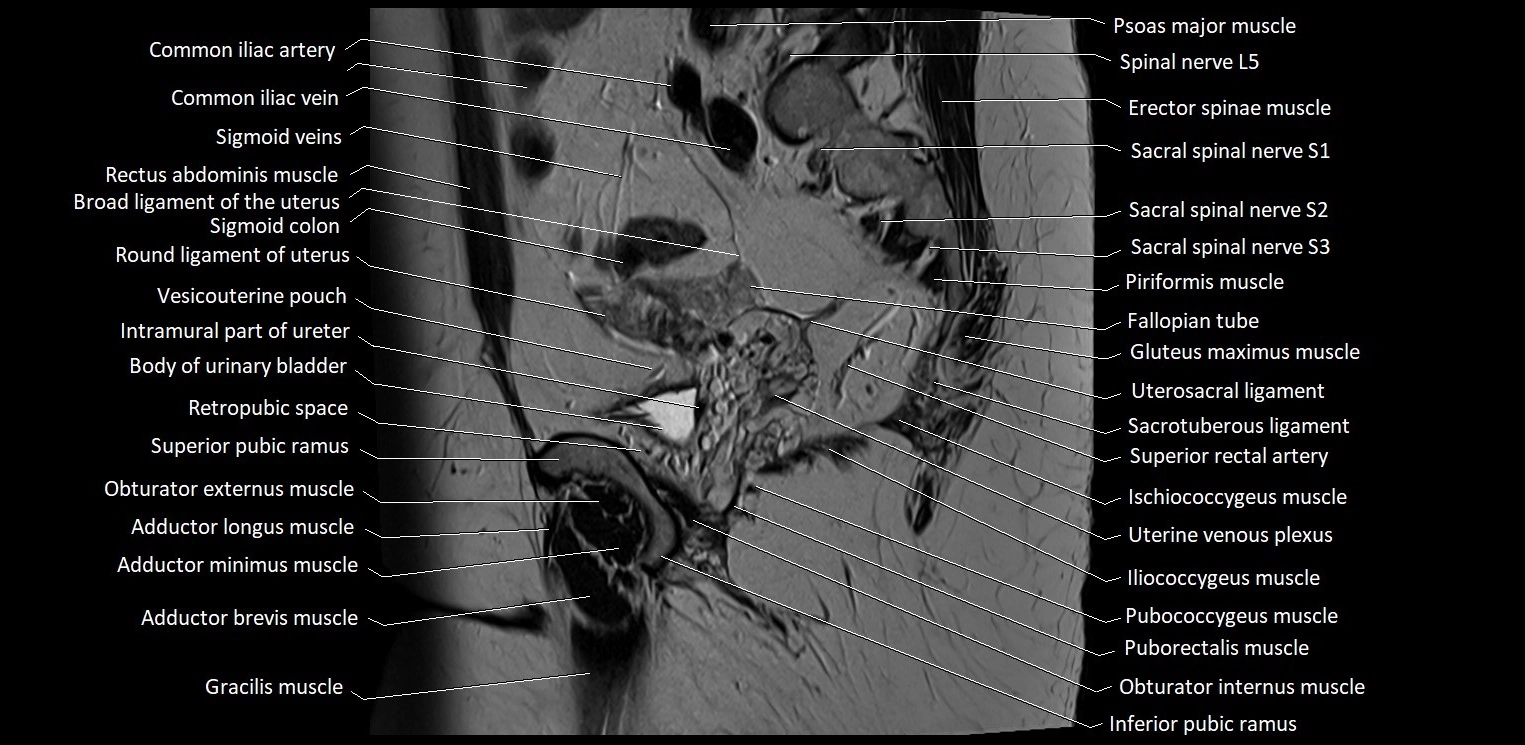

- Body of urinary bladder

- Broad ligament of uterus

- Fallopian tube

- Gracilis muscle

- Iliococcygeus muscle

- Iliopsoas muscle

- Iliopsoas tendon

- Inferior pubic ramus

- Inguinal ligament

- Obturator externus muscle

- Obturator internus muscle

- Pectineus muscle

- Piriformis muscle

- Psoas major muscle

- Pubic symphysis

- Pubococcygeus muscle

- Puborectalis muscle

- Retropubic space

- Round ligament of uterus

- Sacral plexus

- Sacrospinous ligament

- Sacrotuberous ligament

- Sigmoid colon

- Spinal nerve L5

- Spinal nerve S1

- Spinal nerve S2

- Spinal nerve S3

- Superior rectal artery

- Uterosacral ligament